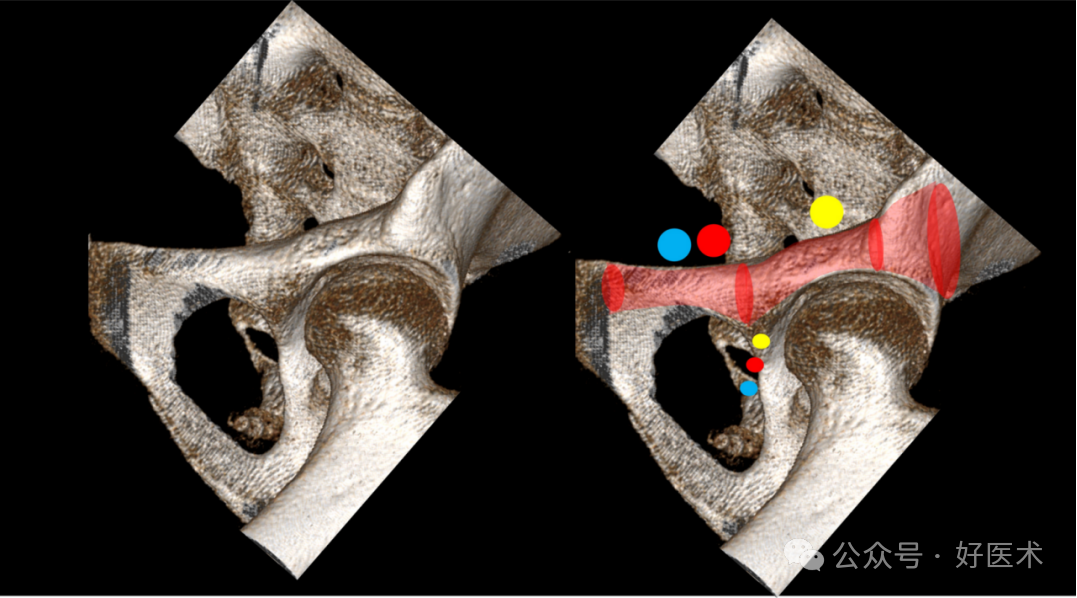

透视图像

在放射影像上,若能够识别髂后皮质骨(骨盆边缘)、髋臼上软骨下骨(髋臼顶)、耻骨中部下骨皮质以及增厚的弯曲的皮质表面,则视为**观察视角。Eastman等人推荐了骨盆入口位(Pelvic Inlet View, PIV)和联合闭孔出口位(Combined Obturator Oblique Outlet View, COOO)。由于个体差异和性别解剖学的不同,没有报告关于影像增强器定位的标准值。此外,不推荐完全重叠的上下耻骨支(通过骨盆超入口位,Pelvic Hyper-Inlet View, PhIV)的影像。使用PIV时,可以看到后上方的耻骨支表面位于后下方耻骨支表面的后方(表现为一个小的闭孔阴影)。这种视角下,耻骨支的中部区域显示不充分。COOO视角是**的,如果它显示了中支区域的**宽度,这需要对图像增强器进行一些微调。Rommens等人还推荐了PAP视角。PIV视角是从“上方”观察,而COOO视角是从侧方观察。推荐的X光摄片顺序包括(图14):

图14 逆行上支螺钉或顺行前柱螺钉的放射影像序列:COOO、高入口位、COOO、COOI和骨盆入口视图,各视图均对应**导针分布区域(彩色显示)。

-COOO:用于确定靠近耻骨结节的进钉点。

-使用PIV视图监视:直至钻头尖端接近(经典的)骨折线。

-COOO:用于确认钻头在关节周围的导向(额外的COOI视角有助于提供第二个平面)。

-PIV:用于显示整个上支内的完整路径。